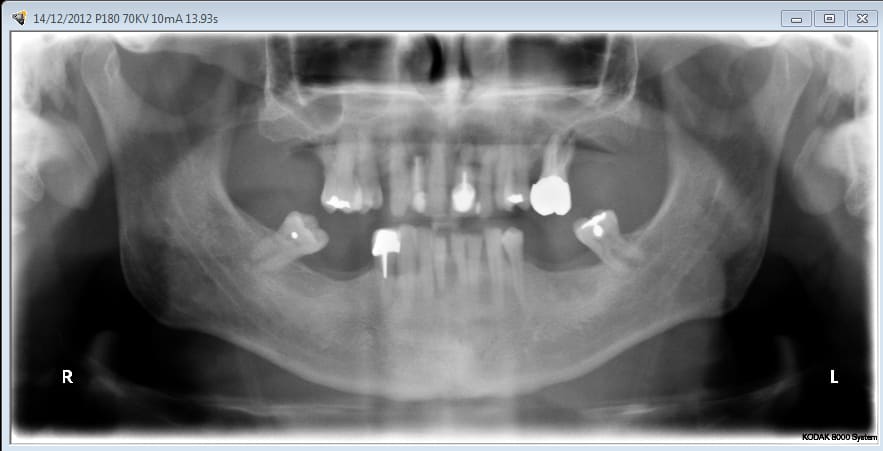

Vous regardez un cas de mci et ne voyez que l’implant sur 9 (je ne parle pas des derniers qui n’ont que quelques jours) qui posé il y a 4 ans lors d’un sinus lift latéral ne va pas bien, et de 2 (8) qu’un 3ème année pourrait enlever.

Ce patient arrivant aujourd’hui en consultation avec la pano initiale, je dirais aussi que mon protocole est nul et il n’a que 4 ans.

Au stade de la pano 1 peut-on sauver les dents ?

Le patient a eu un traitement paro suivi d’une contention ortho. Une option était exo 11 21 25 et bridge 15 à 25, mais 13 14 15 étaient latéro déviées cela se devine sur la photo que Noah a reprise.

planif cas 1

contrôle d'un des cas à 1 mois